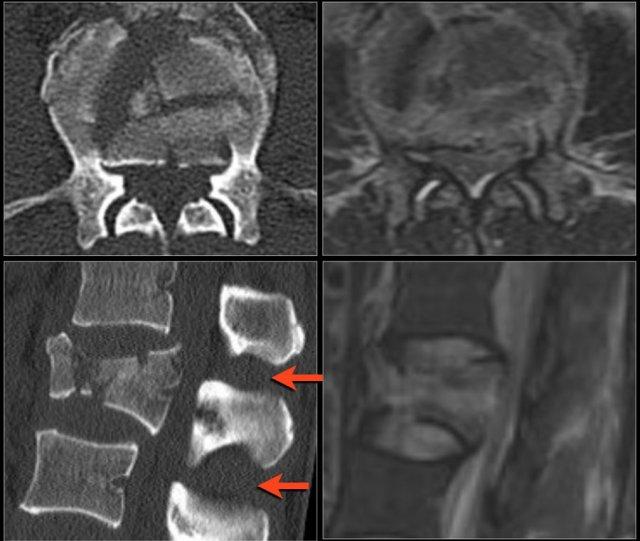

Cột sống cứng

Bệnh nhân có cột sống cứng (như trong viêm cột sống dính khớp, DISH và viêm khớp dạng thấp) dễ bị gãy xương cột sống hơn, ngay cả sau chấn thương nhẹ (6).

Vôi hóa dây chằng cột sống và vôi hóa vòng sợi thay đổi cơ sinh học của cột sống, tạo ra các cánh tay đòn dài và hạn chế khả năng hấp thụ ngay cả các va chạm nhỏ.

Xương thường rất loãng.

Các hình ảnh là của một bệnh nhân với hình ảnh cột sống tre điển hình do viêm cột sống dính khớp.

Sau khi ngã ngửa, không thấy gãy xương trên phim X-quang.

Tuy nhiên, CT cho thấy một đường gãy mảnh qua mặt trước thân đốt sống và cả qua mỏm gai.

Tiếp tục xem các hình ảnh MRI.